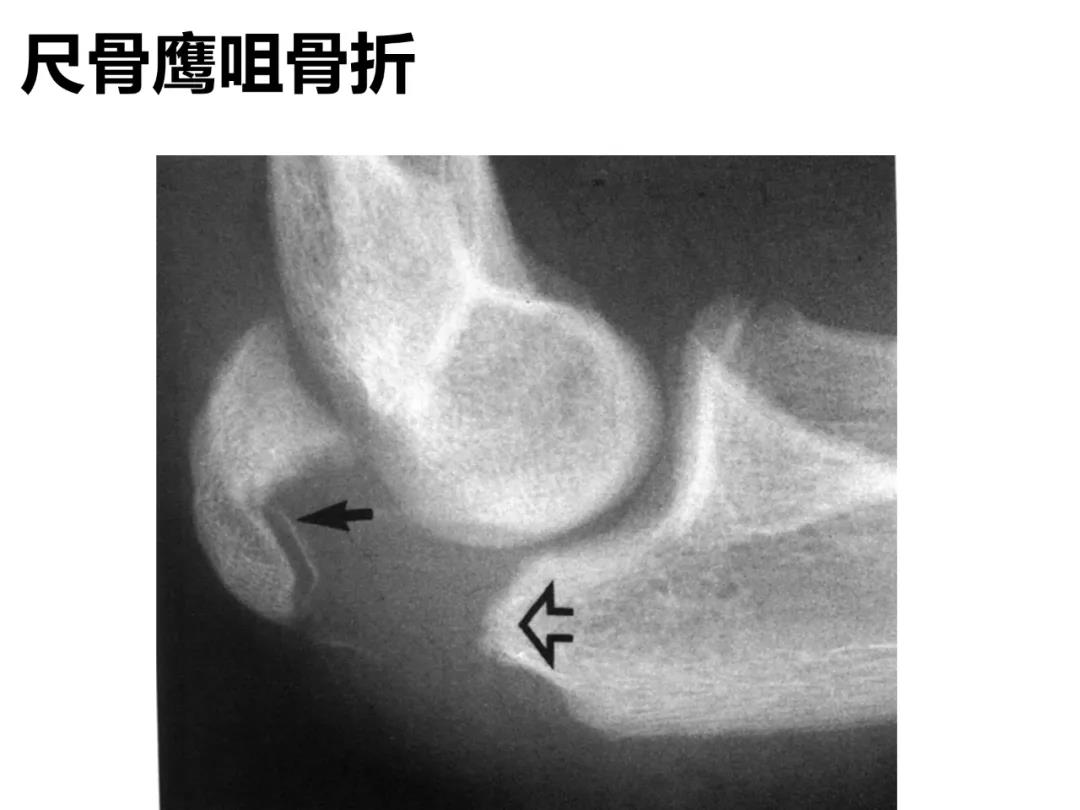

小儿骨科X线片汇总,临床读片宝典!